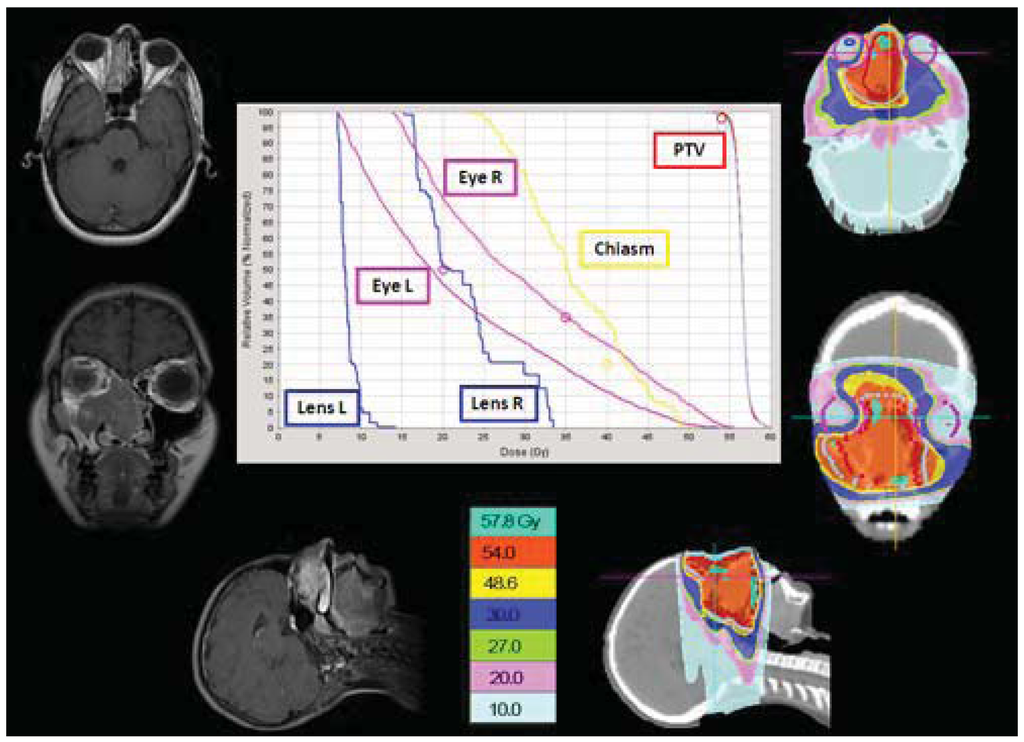

In our patients with head and neck tumors the use of HT, as an alternative to 3D-CRT, was chosen to avoid multiple fields, different energies, and junctions and to spare unavoidably higher dose to the optic nerves, chiasm, eyes and lens, as shown in our adolescent patient affected by esthesioneuroblastoma of the nasal cavity (Figure 5). HT gives us the opportunity to “paint” the high-dose region around the target volume and thus spare at least part of the mucosa from the high-dose region.

Cases like this demonstrate that HT-delivered IMRT may provide superior dose homogeneity and dose conformality when compared to earlier technologies, such as 3D-CRT or conventional RT, leading to efficient sparing of the spinal cord, the parotids, the teeth and the mandible.